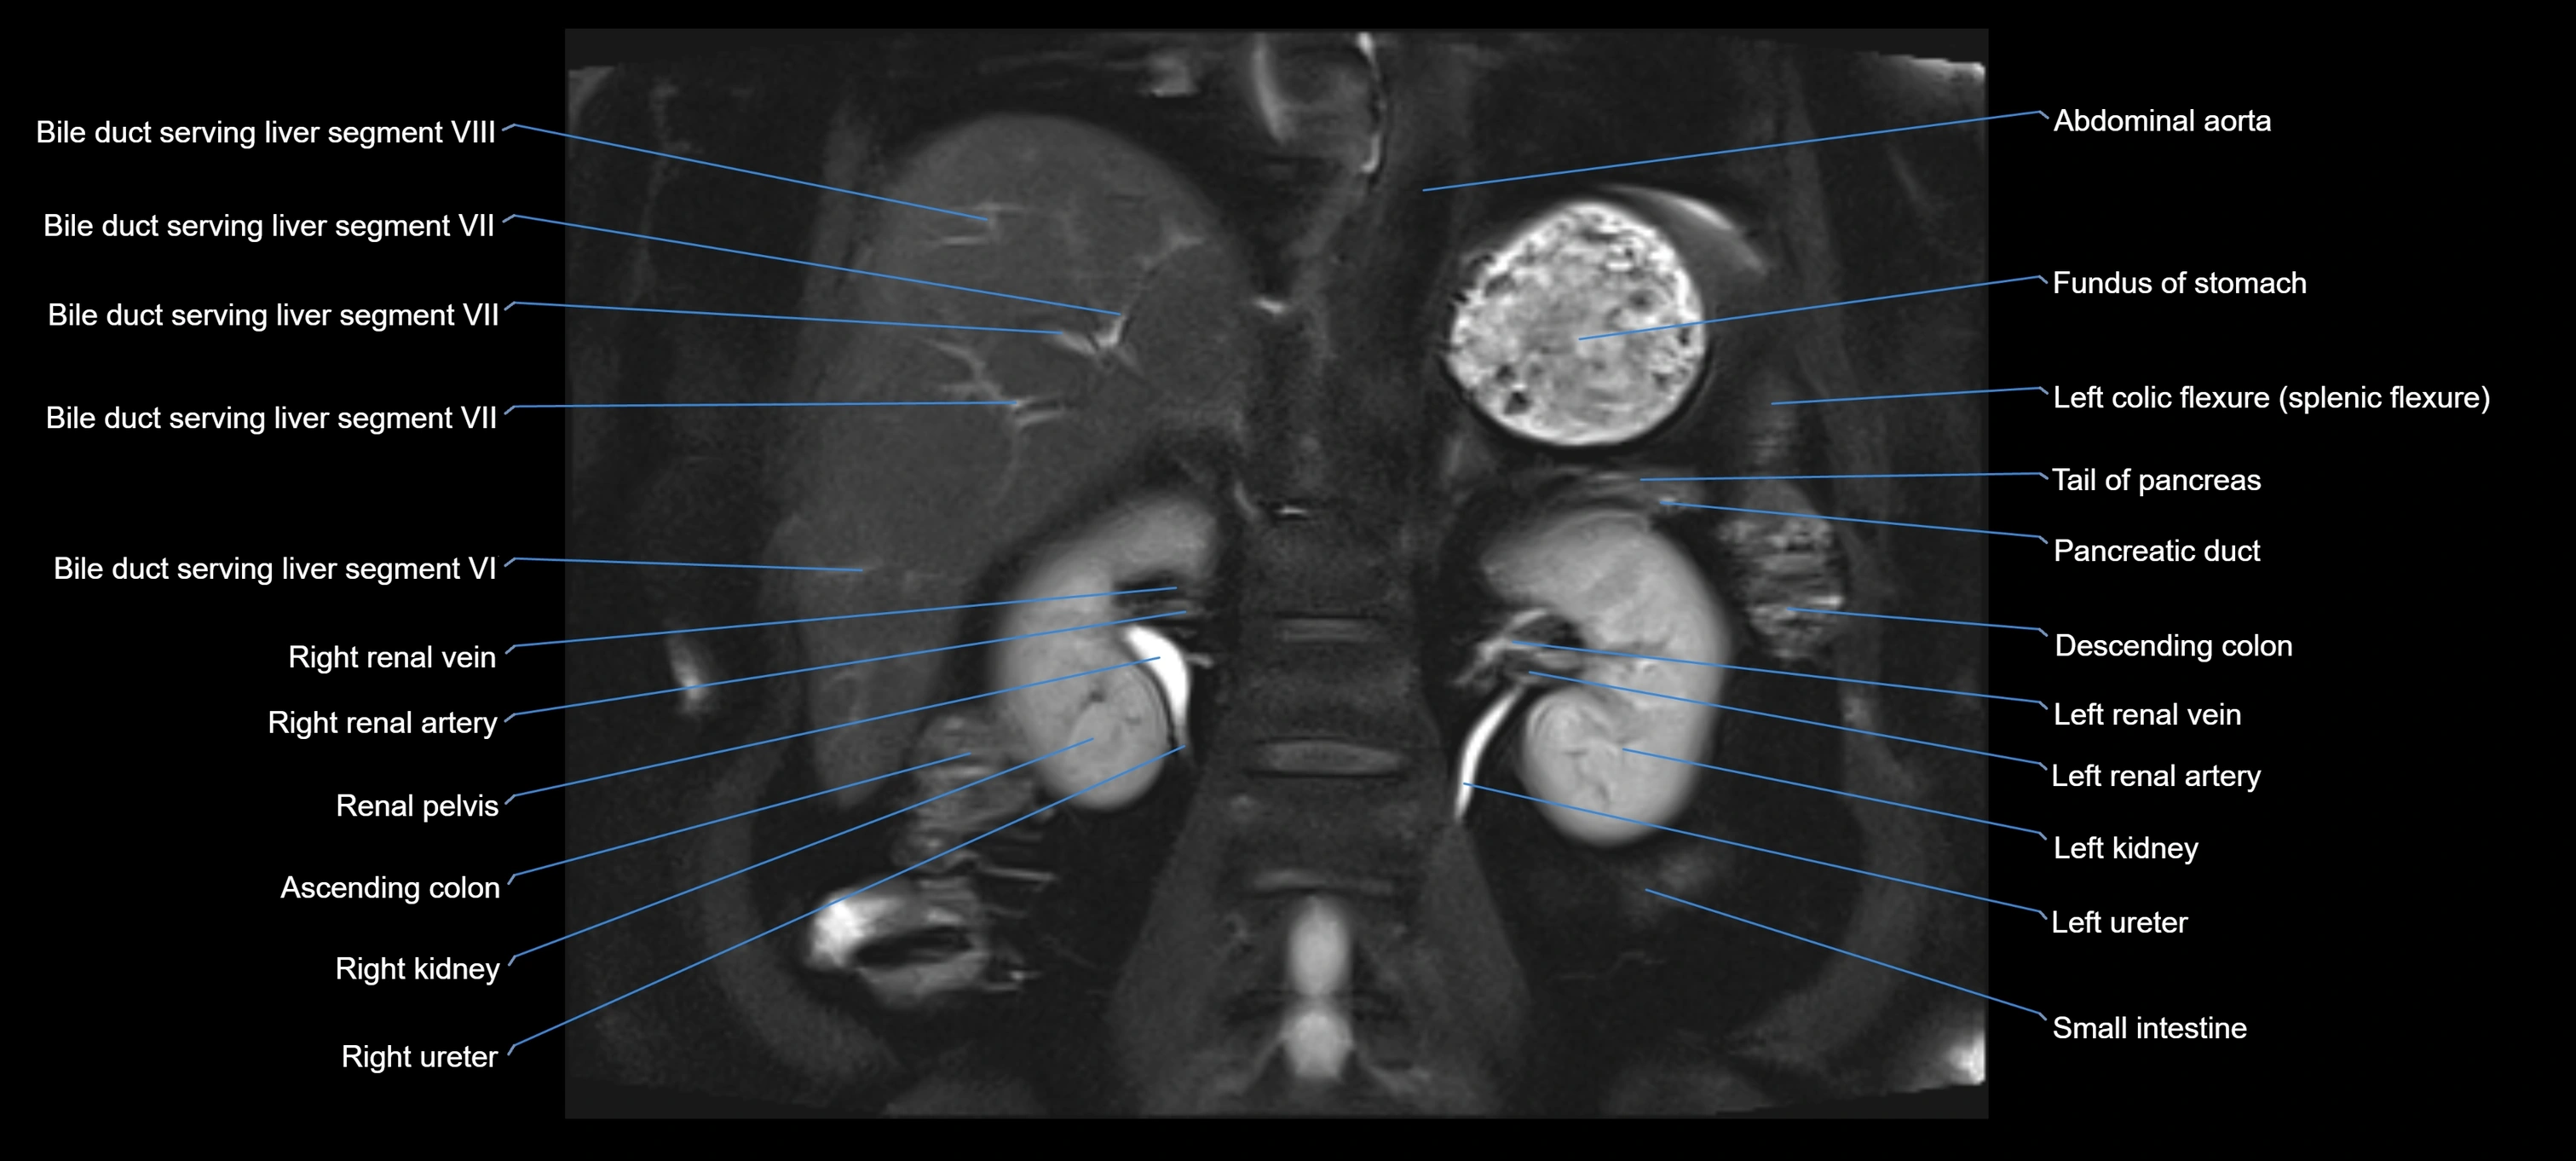

MRI Appearance

T1-weighted images:

• Not typically visualized unless dilated; appears as low signal tubular structure if seen

• Surrounding pancreatic parenchyma shows intermediate signal

T2-weighted images:

• Duct fluid appears bright

• Accessory duct seen as a fine high-signal tubular structure in pancreatic head

STIR (Short Tau Inversion Recovery):

• Duct fluid remains bright

• Surrounding fat suppressed, improving duct conspicuity

T1 Fat-Sat Post-Contrast:

• Normal duct does not enhance

• Surrounding inflammatory or neoplastic changes may enhance

T2 Fat-Saturated HASTE (single-shot):

• Accessory duct: bright, thin linear structure in pancreatic head

• Stones, strictures, or air bubbles appear as dark filling defects

• Excellent for rapid evaluation of duct patency

T2 TSE Fat-Saturated 3D (MRCP sequence):

• Duct visualized as a continuous bright tubular structure joining or parallel to the main pancreatic duct

• Allows 3D reconstruction of ductal anatomy and variants

• Excellent for diagnosis of pancreas divisum

Thick-slab T2 Fat-Saturated HASTE:

• Shows the accessory duct as part of the biliary–pancreatic system in a projectional image

• Highlights communication with main pancreatic duct and opening into the minor papilla

• Filling defects (stones, strictures) seen as dark spots within bright fluid

MRI image

image

Fullscreen Image